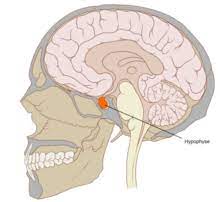

Dabei wird die Hypophyse als Ausführungsorgan bezeichnet denn diese übernimmt die Rolle der Freisetzung. Trotz ihrer Größe ist sie eine äußerst wichtige Drüse. Die Hypophyse befindet sich unter dem Gehirn und ist eine erbsengroße endokrine Drüse die in einer knöchernen Tasche in der Schädelbasis sitzt die als Hypophysenfossa bezeichnet wirdDie Hypophysenfossa ist auch als Sella Turcica bekannt was übersetzt türkischer Sattel bedeutet da sie einem Sattel mit Stützen vorne und hinten ähnelt die vom türkischen Volk.

Sie bilden das kleine Machtzentrum in unserem Gehirn das Descartes als Sitz unserer Seele definierte. Der griechische Name Hypophyse bedeutet wörtlich das unten anhängende Gewächs. Die Hypophyse steuert die Funktion der meisten Drüsen die ihre. Die Hypophyse selbst ist nur so groß wie ein Kirschkern und besteht aus zwei Teilen mit unterschiedlicher Funktion. Hypophyse Hormondrüse im Türkensattel. Die Hypophyse ist eine winzige Drüse nicht größer als eine Erbse die sich an der Unterseite des Gehirns befindet. Trotz ihrer Größe ist sie eine äußerst wichtige Drüse. Wenn Tumoren auf die Hypophyse drücken stören sie die Hormonbildung. Sie sitzt auf der Sella turcica Türkensattel einer Vertiefung der Schädelbasis mitten in unserem Schädel etwa auf Höhe der Nase und der Ohren.

Wenn Tumoren auf die Hypophyse drücken stören sie die Hormonbildung. Die Geheimnisse des menschlichen Körpers sind seit Jahrhunderten nicht mehr ausgetrocknet. Lage und Aufbau der Hypophyse. Sie ist in zwei Bereiche geteilt. Unsere Masterdrüse die Hypophyse stellt einige Hormone her fungiert aber auch als Vermittler zwischen dem. Hypophyse Hormondrüse im Türkensattel. Excel wenn addition wenn wert größer null ist.